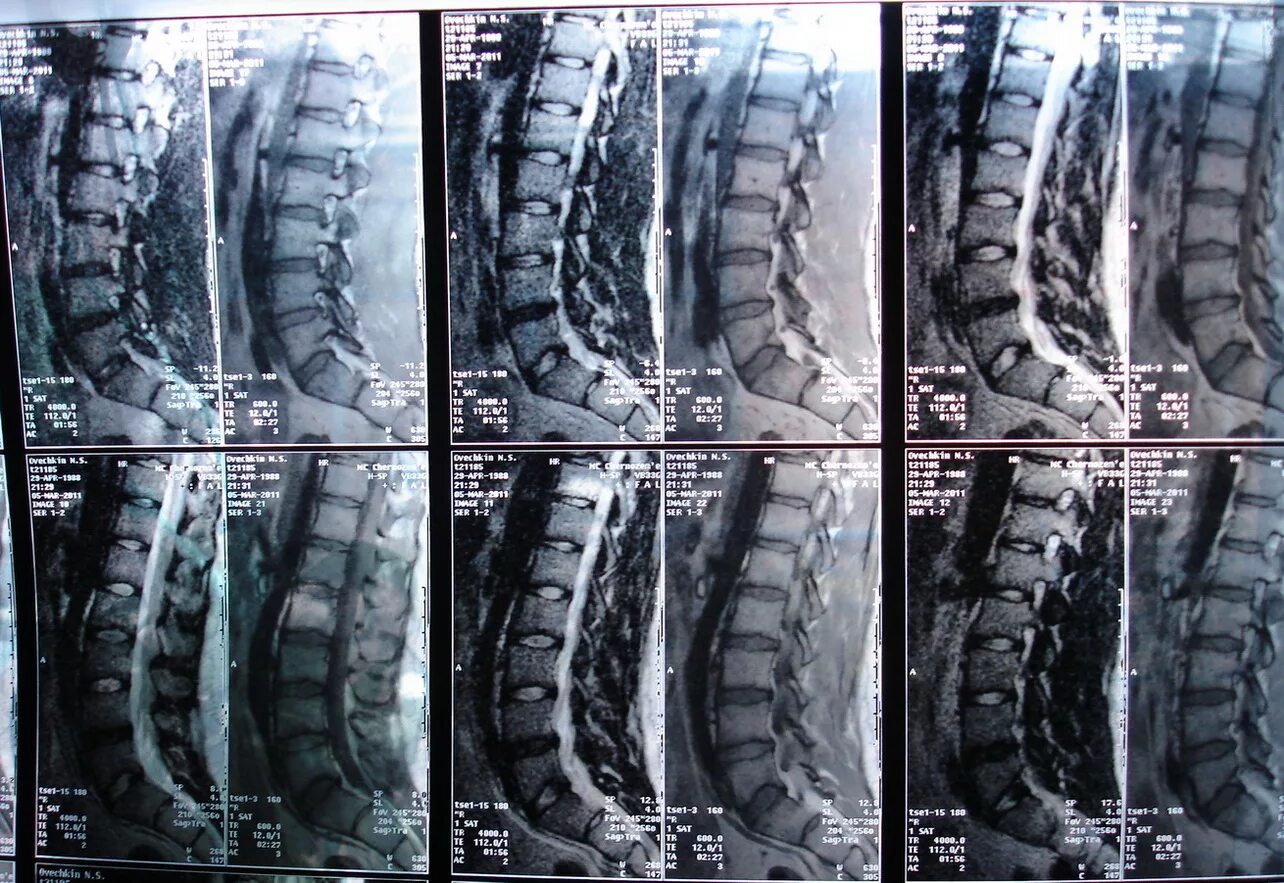

Протрузия дисков l3 4 5